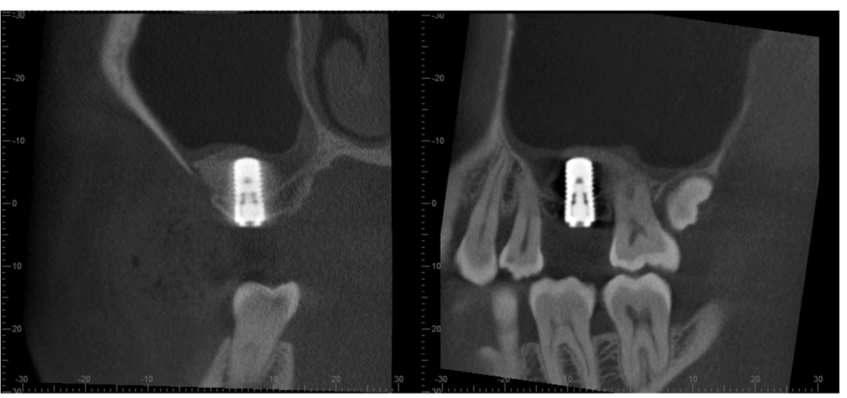

术后当天CBCT,三维方向显示种植体周围及种植体顶部均有充填的骨粉,上颌窦底黏膜完整,提升效果良好(图5)。

图5 术后当天CBCT

术后8个月,CBCT可以在三维方向清楚地显示种植体周围及种植体顶部均有骨组织结合(图6),提示可以完成上部结构修复(图7)。

图6 术后8个月

外提升6个月后植入种植体,CBCT示骨增量效果明显(图21)。

图21 种植术后CBCT三维影像A.矢状位;B.冠状位;C.水平位

术后当天CBCT,三维显示人工骨充填情况,窦底黏膜完整,窦腔内无积液,骨增量效果良好(图26)。

图26 术后当天CBCTA.矢状位;B.冠状位;C.水平位

外提升术后6个月复诊,CBCT示人工骨区域骨密度增强,骨质形成佳,可以进行种植体植入(图27)。

图27 外提升术后6个月CBCT矢状位及冠状位见人工骨植入位置及形态好